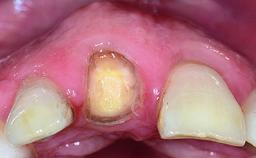

A 32-year-old female Caucasian patient with a compromised maxillary right central incisor was referred to us by a general dentist. Her chief complaints were discomfort and mobility of tooth 11 with unsatisfactory esthetics due to discoloration. The patient reported a previous trauma, some years earlier, as the origin of pathology on the afflicted tooth. Anamnesis was negative for any other dental or periodontal pathology in the remaining dentition. The patient did not take any medication and reported to be a light smoker (5–10 cigs/day). She had high esthetic expectations of her treatment. The extraoral examination revealed a high smile line with full exposure of her maxillary teeth and surrounding soft tissue in the area between the second premolars.

Soft Tissue Contour and Volume Slightly compromised